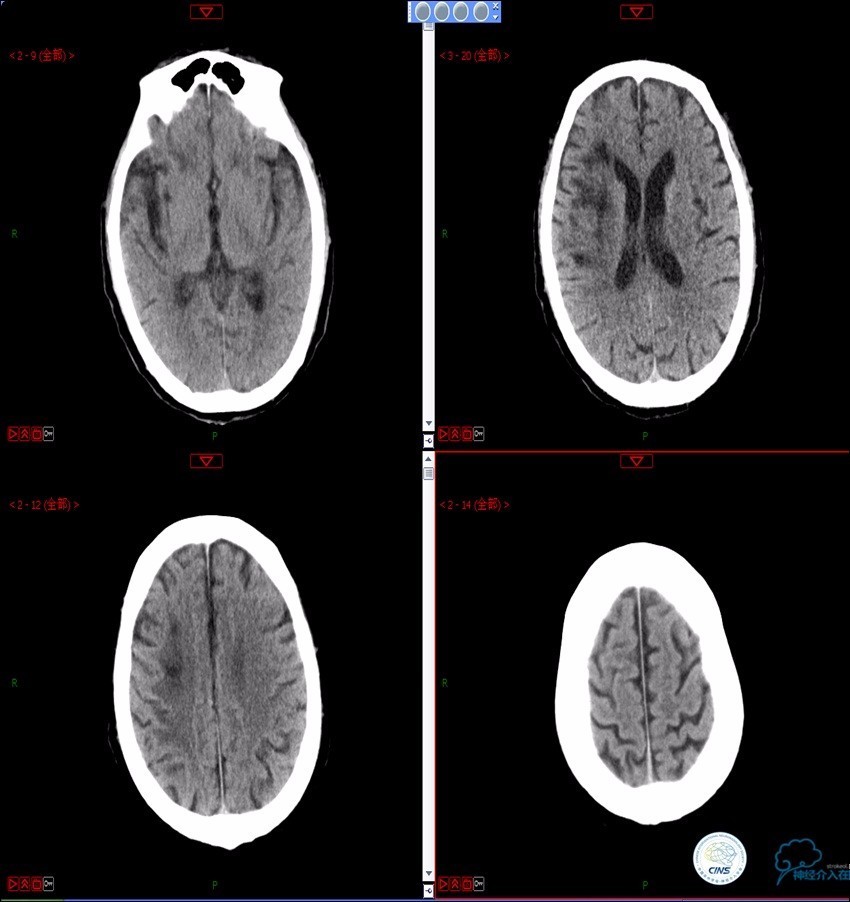

》术后三小时,患者出现恶心呕吐,伴有意识丧失。

》出血原因?侧支代偿不佳!

颈动脉次全闭塞 术前评估

头颅灌注: 注意两侧CBF CBV的对比。

DSA:注意侧支代偿。